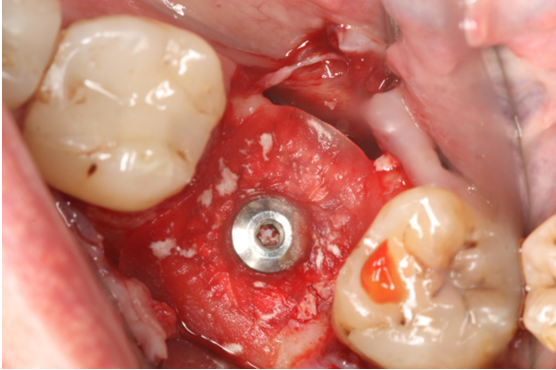

7. Χειρουργική Θεραπεία Περιεμφυτευματίτιδας

Ασθενής ετών 57 προσήλθε στο ιατρείο παραπονούμενος για ήπιο πόνο, φλεγμονή και πυορροή στο εμφύτευμα που είχε τοποθετηθεί προ τριετίας. Κλινικά και ακτινογραφικά διαπιστώθηκε οστική απώλεια γύρω από το εμφύτευμα (οστική βλάβη- κρατήρας). Ακολούθησε χειρουργική διάνοιξη στην περιοχή, καθαρισμός του εμφυτεύματος, τοποθέτηση οστικού μοσχεύματος και μεμβράνης (οστική ανάπλαση).

Έξι μήνες μετά κλινικά η βλάβη έχει επαλειφθεί και ακτινογραφικά εμφανίζεται οστική πλήρωση αυτής.

Περιεμφυτευματική βλάβη - Αρχική Κλινηκή Εικόνα

Περιεμφυτευματική βλάβη (ανάπλαση)